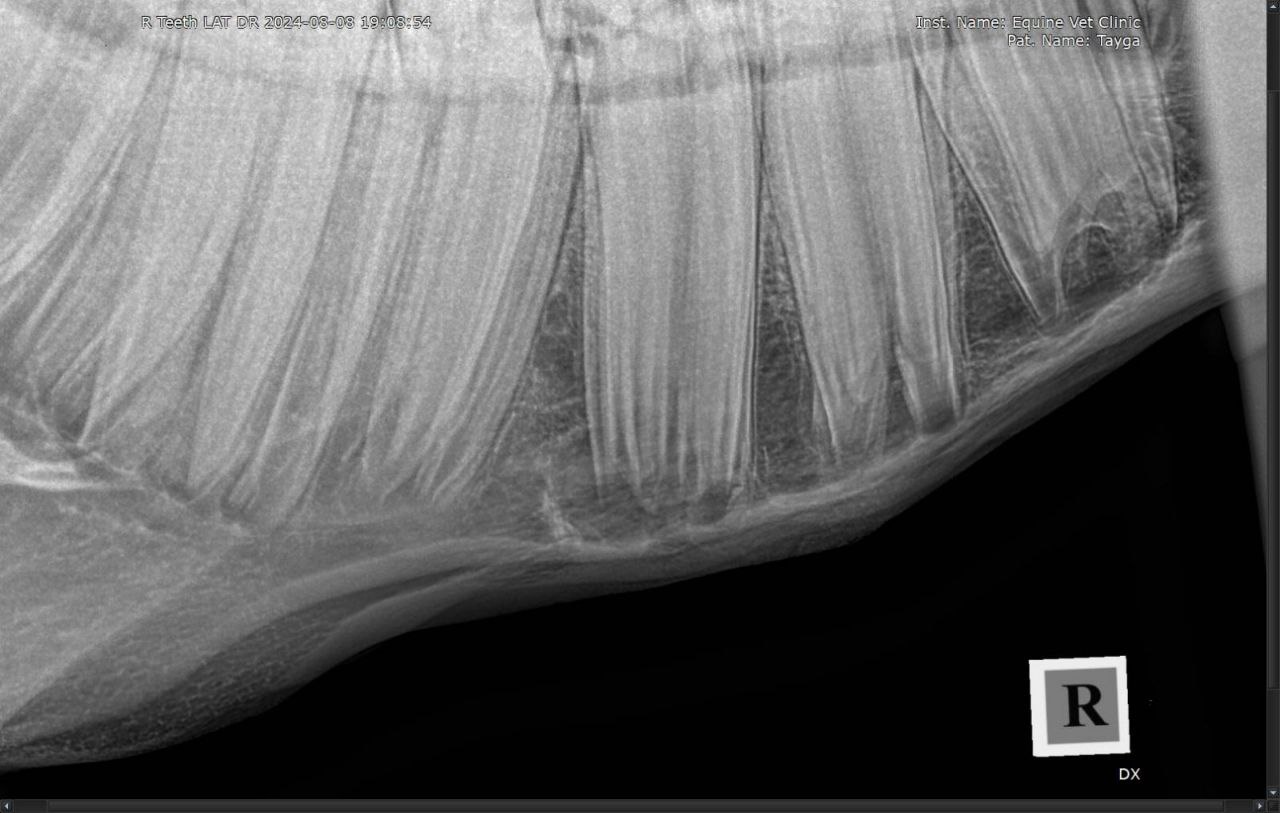

Результаты рентгенологического исследования: наблюдается неравномерная рентгенологическая плотность вокруг верхушки корня и утолщение кортикальной зоны кости нижней челюсти в проекции 408 зуба. Зондированием свища в нижней челюсти установлена вовлеченность корня 408 зуба в формировании канала свища.